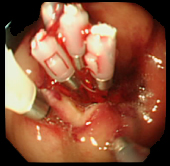

| 症例(胃ポリープ切除1) | |||

| ポリープ | 根元に生理食塩水を注入して水ぶくれ状態をつくり、膨らんだその部分に スネアをかけて高周波の電流を流し病変部を焼き切っている状態。 |